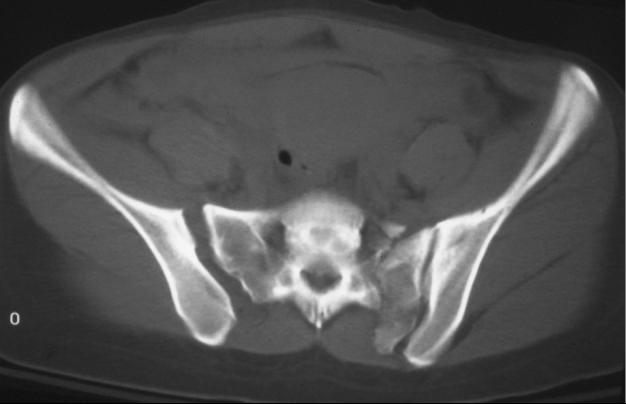

Sacroiliac Joint Icd 10. Bilateral lower leg joint pain; Bilateral inflammation of sacroiliac joint;

Sacrococcygeal disorders, not elsewhere classified. Sacroiliac (si) joint osteoarthritis icd 10 overview sacroiliac (si) joint osteoarthritis icd 10 severe joint pain is one of the most common ailments among older adults. It is more common in individuals who are 45 to 64 years of age and among people of all races.

Dislocation And Sprain Of Joints And Ligaments Of Lumbar Spine And Pelvis (S33) Sprain Of Sacroiliac Joint, Initial Encounter (S33.6Xxa) S33.6.

Sacroiliitis can cause pain in your buttocks or lower. It is more common in individuals who are 45 to 64 years of age and among people of all races. Bilateral lower leg joint pain;

It contains codes for diseases, signs and symptoms, abnormal findings, complaints, social circumstances, and external causes of injury or diseases. Inflammation of left sacroiliac joint; Sacroiliac joint arthropathy icd 10 will sometimes glitch and take you a long time to try different solutions.

Unspecified inflammatory spondylopathy, sacral and sacrococcygeal region. This condition is also more What is the icd 10 code for right sacroiliitis?

Sacrococcygeal disorders, not elsewhere classified. Bilateral inflammation of sacroiliac joint; It is more common in individuals who are 45 to 64 years of age and among people of all races.

Dislocation of sacroiliac and sacrococcygeal joint, init; What is the icd 10 code for sacroiliac joint dysfunction? 551 medical back problems with mcc;